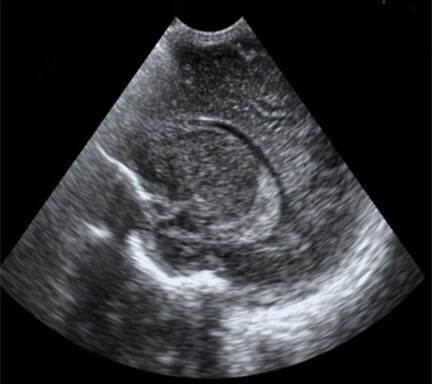

Neonatology Artifact 2 Image